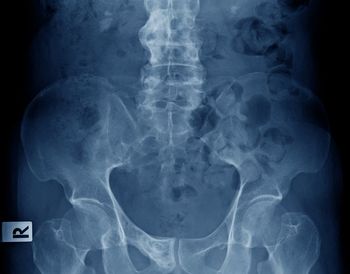

An international physician group writing in the British journal Annals of the Rheumatic Diseases, has updated recommended parameters that constitute lesions in the sacroiliac joints of patients with spondyloarthritis. The definitions of capsulitis, enthesitis, fat lesion and erosion were revised and new definitions were developed for joint space enhancement, joint space fluid, fat metaplasia in an erosion cavity, ankylosis and bone bud.

In this slideshow, we highlight 12 recommendations for assessing MRI lesions on the sacroiliac joints of patients with spondyloarthritis. The recommendations were made by the Assessment of Spondyloarthritis International Society (ASAS) MRI working group and published in the British journal Annals of the Rheumatic Diseases earlier this year.

Bone erosion, fat in joint spaces (backfill), and ankylosis visible on MRI could help identify women with axial spondyloarthritis, investigators wrote in a research article published last month in Arthritis & Rheumatology.